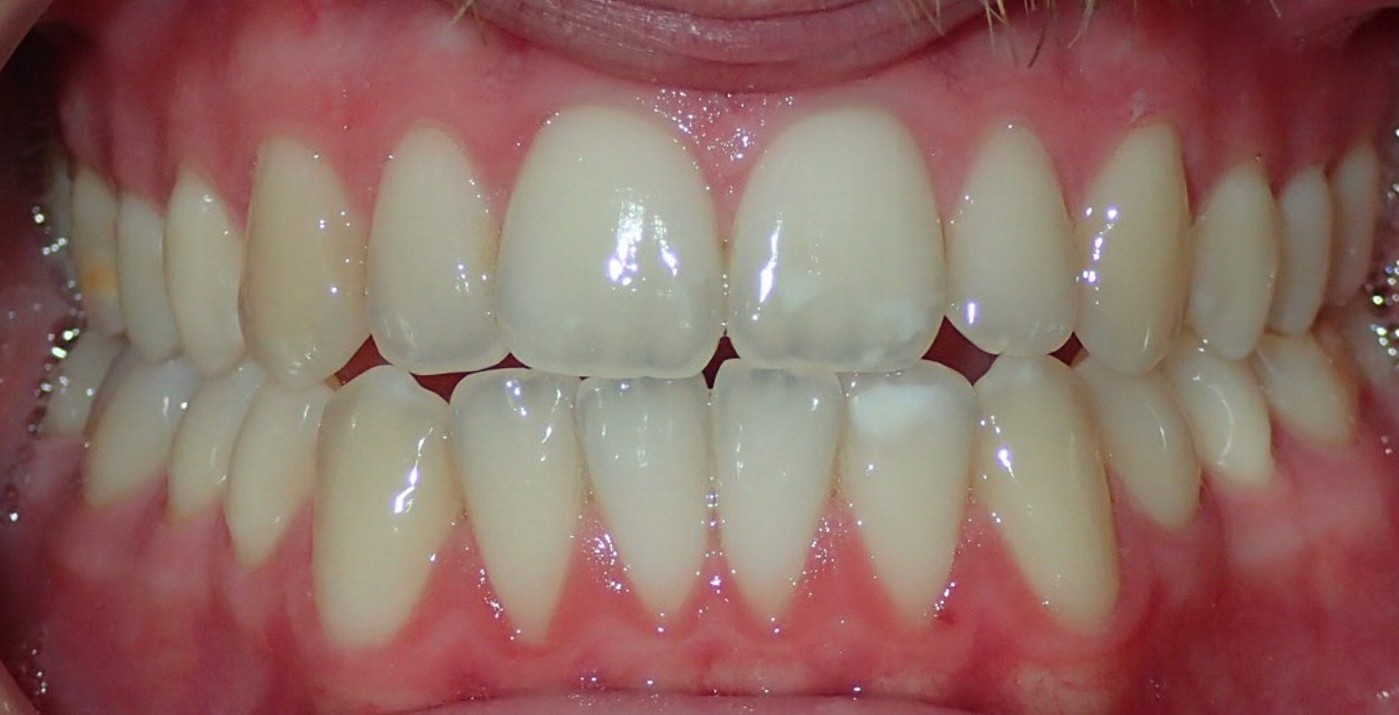

Diagnosis: Class III malocclusion, edge-to-edge anterior relationship, lower anterior crowding

Initial treatment

INTRAORAL